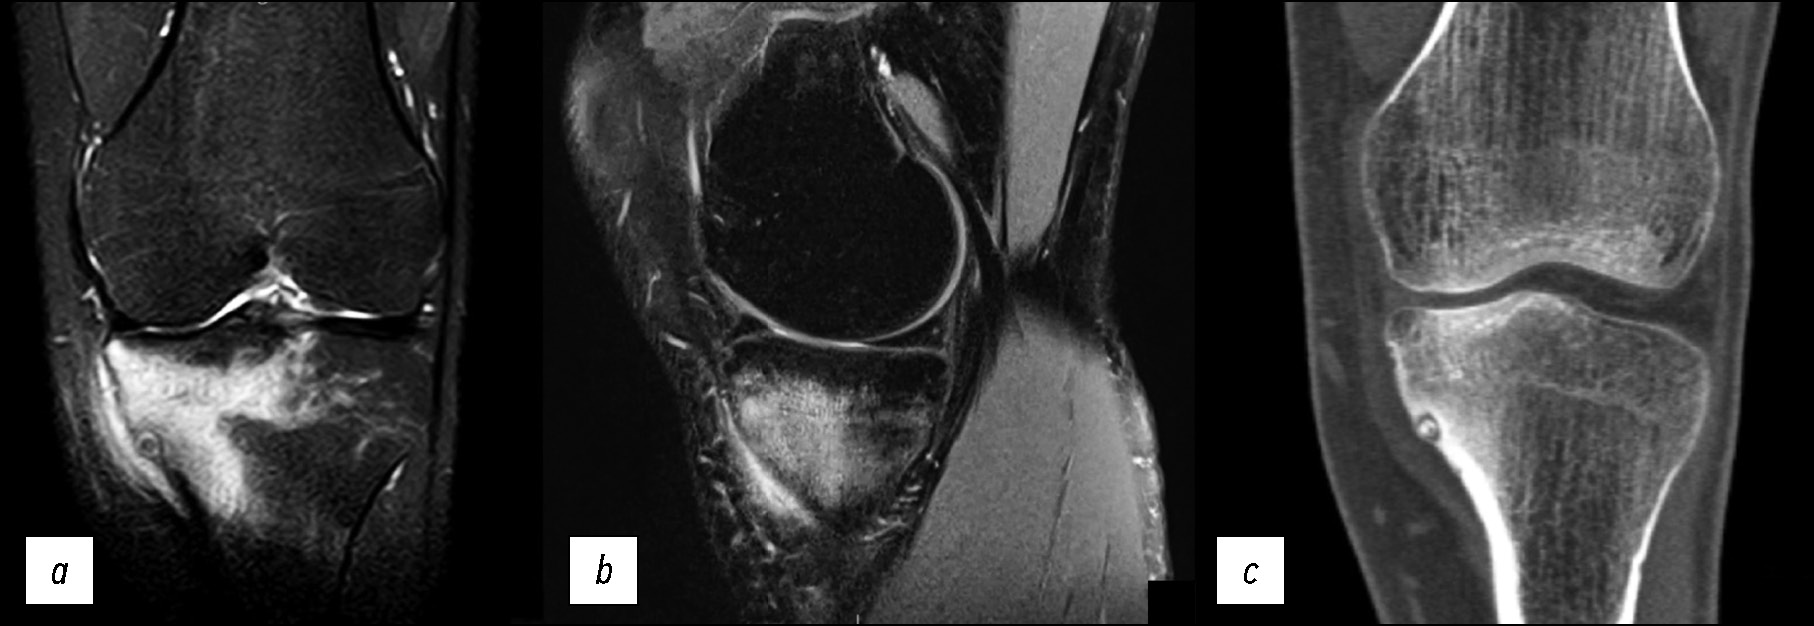

На выполненных рентгенограммах патологии не выявлено. Пациент наблюдался в клинике по месту жительства с диагнозом «остеоартрит коленного сустава». В связи с неэффективностью применения нестероидных противовоспалительных препаратов выполнил МРТ-исследование, на котором выявлен отёк костной ткани в области наружного мыщелка бедренной кости (рис. 1), плавно переходящий на внутренний мыщелок.

Рис. 1. МР-томограммы коленного сустава: а, b — изображение в T2w-STIR режиме, с — изображение в режиме Т1 в корональной проекции, и графическое изображение остеонекроза мыщелка в сагиттальной проекции (d).

Fig. 1. MR images of the knee: а, b — T2-weighted short-tau inversion recovery (T2w-STIR), с — T1-weighted sequences in the coronal projection and a graphic image of an osteonecrosis (d).

Состояние расценено как идиопатический асептический некроз наружного мыщелка бедренной кости I стадии по классификации ARCO (остеонекроз) (M87.0) [8].

Особенности отёка костной ткани: достаточно равномерный, без каких-либо линий и включений, распространяется на большую часть мыщелка. Гиалиновый хрящ не вовлечён в патологический процесс, имеет ровную поверхность без деформации, что характерно для начальной стадии асептического некроза [9].